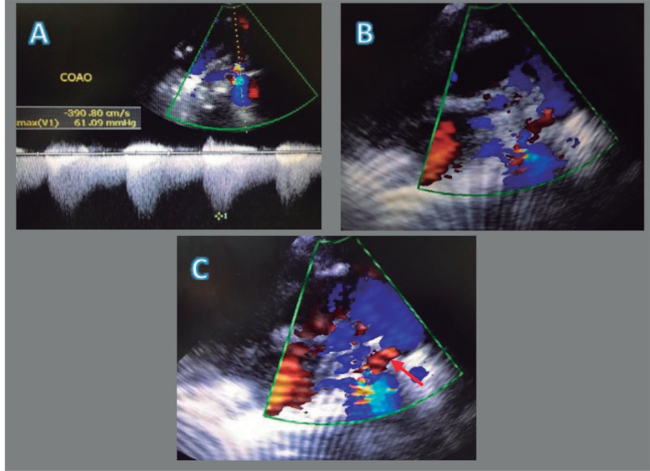

Posteriormente, se logra la extubación y el paciente pasa a cuidados intermedios donde permanece estable durante 8 h aproximadamente. De forma súbita, presenta deterioro cardiovascular y respiratorio (score Downes 8) que requiere nuevamente VMA con parámetros elevados. Debido a la abrupta aparición de la sintomatología mencionada, se solicita un ecocardiograma que reportó una posible CoAo, por un gradiente de presión de 61 mmHg más corrida diastólica y presión pulmonar de 37 mmHg (Figura 1 A-C). Se solicita una angiotomografía contrastada de tórax, que reportó una estenosis grave de la aorta descendente después de la arteria subclavia izquierda con discreta dilatación posestenótica de la aorta descendente (11 mm), tortuosidad y dilatación de las arterias mamarias internas derecha e izquierda, además de las arterias intercostales (Figura 2 A-C). A los 11 días de vida, el servicio de cirugía cardiotorácica realiza una coartectomía ampliada más anastomosis término-terminal sin complicaciones.